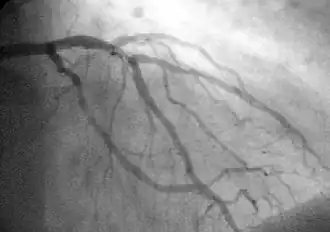

Coronary catheterization

Coronary catheterization uses pressure monitoring and blood sampling through a catheter inserted into the heart through blood vessels in the leg or wrist to determine the functioning of the heart, and, following injections of radiocontrast dye, uses X-ray fluoroscopy, typically at 30 frames per second, to visualize the position and volume of blood within the heart chambers and arteries. Coronary angiography is performed during a cardiac catheterization and used to determine the patency and configuration of the coronary artery lumens.